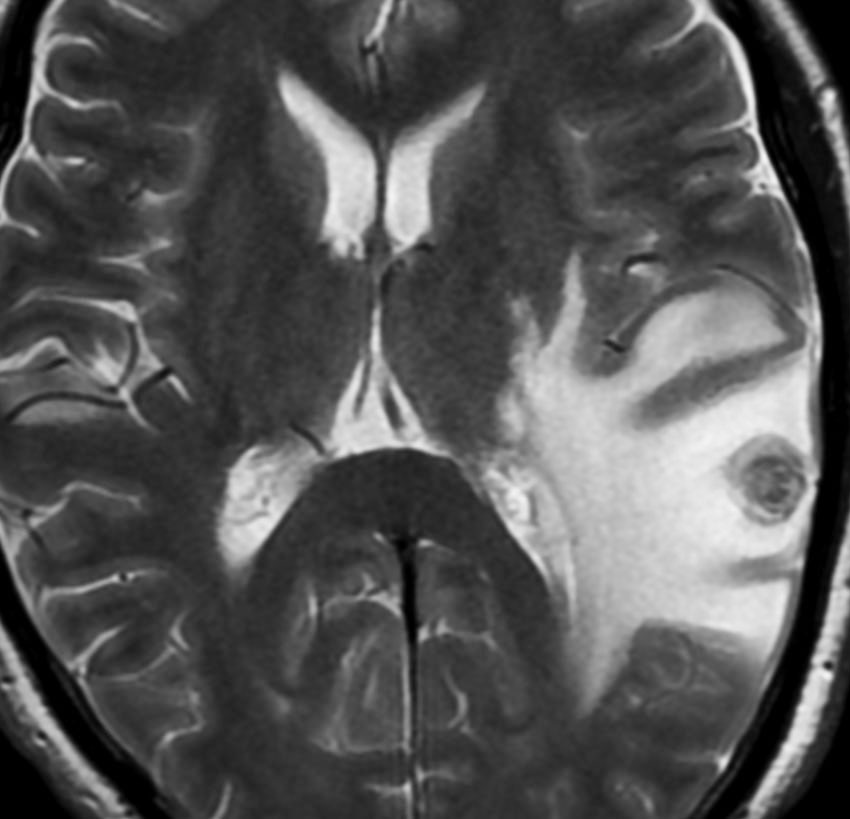

乳癌の多発脳転移の例

全脳照射3ヶ月後のMRIです。左の頭頂葉の転移巣は消失していますし,左の小脳転移は手術摘出できていて再発もありません。このように乳癌は,多発転移であっても比較的に制御しやすいものです。しかし,一度消えた病巣が再発したり,また新たなところに脳転移が生じるという可能性もあります。

髄膜癌腫症(癌性髄膜炎)

leptomeningeal carcinomatosis, carcinomatous meningitis

脳と脊髄の表面にがん細胞が広範に広がって増殖します。MRIでは,矢印のように脳溝 sulciの中に癌の増殖が見られます。T1ガドリニウム増強で,脳溝や脳の表面が白い線のように描出されます,脳血管とは違うのでわかります。

肺小細胞癌の転移 multiple metastases of lung small cell cancer

左のMRIは,肺小細胞癌の患者さんに脳転移が無いか確かめるために撮影されたものです。転移はありませんでした。右側のMRIは,そのわずか3週間後に撮影したものです。数十個の脳転移がありました。肺小細胞癌では短期間の間に無数の脳転移を生じることがあります。かつては脳転移を予防するための予防的全脳照射という治療が行われていたくらいです。